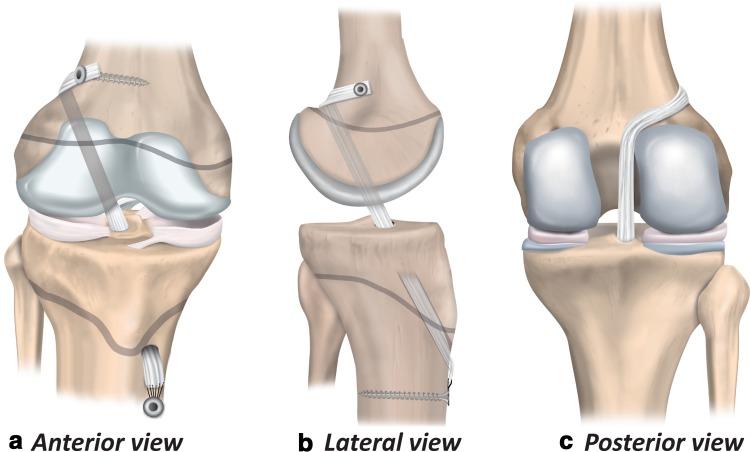

In October 2017, the International Olympic Committee hosted an international expert group of physiotherapists and orthopaedic surgeons who specialise in treating and researching paediatric anterior cruciate ligament (ACL) injuries. Representatives from the American Orthopaedic Society for Sports Medicine, European Paediatric Orthopaedic Society, European Society for Sports Traumatology, Knee Surgery and Arthroscopy, International Society of Arthroscopy Knee Surgery and Orthopaedic Sports Medicine, Pediatric Orthopaedic Society of North America, and Sociedad Latinoamericana de Artroscopia, Rodilla y Deporte attended. Physiotherapists and orthopaedic surgeons with clinical and research experience in the field, and an ethics expert with substantial experience in the area of sports injuries also participated. Injury management is challenging in the current landscape of clinical uncertainty and limited scientific knowledge. Injury management decisions also occur against the backdrop of the complexity of shared decision-making with children and the potential long-term ramifications of the injury. This consensus statement addresses six fundamental clinical questions regarding the prevention, diagnosis, and management of paediatric ACL injuries. The aim of this consensus statement is to provide a comprehensive, evidence-informed summary to support the clinician, and help children with ACL injury and their parents/guardians make the best possible decisions.

2017 年 10 月,国际奥林匹克委员会举办了一次国际专家组会议,参会者包括专门治疗和研究儿科前交叉韧带(ACL)损伤的物理治疗师和骨科医生。美国运动医学骨科协会、欧洲儿科骨科协会、欧洲运动创伤学、膝关节外科和关节镜学会、国际关节镜膝关节外科和骨科运动医学学会、北美小儿骨科协会和拉丁美洲关节镜、膝盖和运动医学协会的代表出席了会议。具有该领域临床和研究经验的物理治疗师和骨科医生,以及一位在运动损伤领域有丰富经验的伦理专家也参与了会议。在目前临床不确定性和有限科学知识的背景下,损伤管理具有挑战性。损伤管理决策还需要考虑与儿童共同决策的复杂性,以及损伤的潜在长期后果。本共识声明针对儿科 ACL 损伤的预防、诊断和管理提出了六个基本的临床问题。本共识声明的目的是提供全面、循证的总结,以支持临床医生,并帮助 ACL 损伤患儿及其父母/监护人做出尽可能最好的决策。